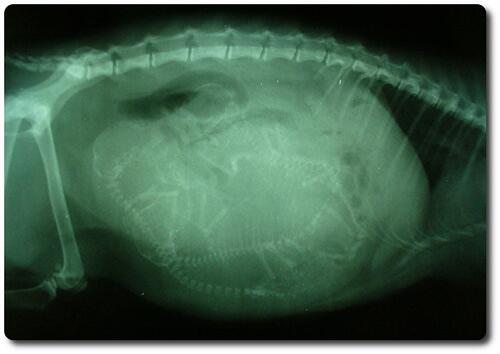

Когда начинать волноваться, если кошка, наоборот, «перехаживает»? «Переношенной» считается беременность сроком более 73 дней. Если вы не знаете точно, сколько времени прошло после зачатия, но кошку наблюдает врач, он примерно определяет срок беременности по УЗИ и (или) рентгеновским снимкам, на основании размеров плодов.

При желании определить состояние здоровья вашей подопечной или количество вынашиваемых котят, вы можете обратиться в ветклинику и пройти рентген или УЗИ. Не забывайте регулярно доставлять вашу подопечную на осмотр к ветеринару

- Рентгеновские снимки — Скелет плодного котенка минерализуется примерно на 42-й день беременности, когда кости становятся видимыми на рентгеновском снимке.

Весь живот вашей кошки можно сфотографировать на рентгеновском снимке, который позволяет ветеринару подсчитать количество котят.Знание того, сколько котят ожидается, важно для того, чтобы ваша кошка родила весь свой помет и в ее матке не осталось котят.

Стоимость этого теста может варьироваться в зависимости от лаборатории вашей ветеринарной клиники. - Рентген: После 45-го дня скелеты у котят кальцинированы и обычно могут быть обнаружены с помощью рентгенографии. Рентген часто используется как средство диагностики беременности и как метод оценки размера помета. Это наиболее часто используемый тест для диагностики беременности у кошек. Стоимость в большинстве случаев колеблется от 150 до 250 долларов.